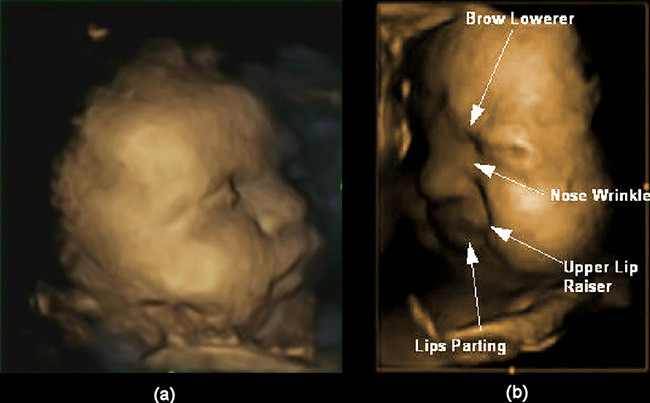

Un estudio realizado con estas ecografías muestra que los bebés hacen en el útero diversas muecas de dolor, expresiones de disgusto, que son las mismas que realizan después de nacer cuando están disconformes con algo o cuando sienten dolor. Según dicen los investigadores, podría ser un ensayo para prepararse para los padecimientos en la vida externa y para lograr hacerlo saber a sus cuidadores, o sea, a sus padres.

Para hacer el estudio hicieron ecografías en 4D a 15 fetos, ocho de ellos niña y siete niños, que fueron observados en cuatro ocasiones en el segundo y tercer trimestre del embarazo. Gracias a esa progresión en el tiempo pudieron ver cómo a medida que la gestación avanzaba las expresiones faciales se hacían más complejas.

Hasta la fecha se sabía que los fetos, debido a la inmadurez, no tenían sensación de dolor antes de las 25 semanas de gestación. En este estudio, sin embargo, se ha observado que a esa "edad" ya muestran expresiones faciales interpretables como muestra de dolor o malestar. Hay que aclarar que en la semana 24 sólo el 5% de las expresiones faciales son de disgusto o dolor, siendo una combinación de 3 gestos, y el 0,3% una combinación de 4 gestos. A las 36 semanas, para comparar, el 21,2% de los gestos que hacen con el rostro son de malestar, con 3 gestos simultáneos, y el 2,8% cuando combinan 4 de los 6 gestos que pueden interpretarse como muecas de dolor o disconformidad.